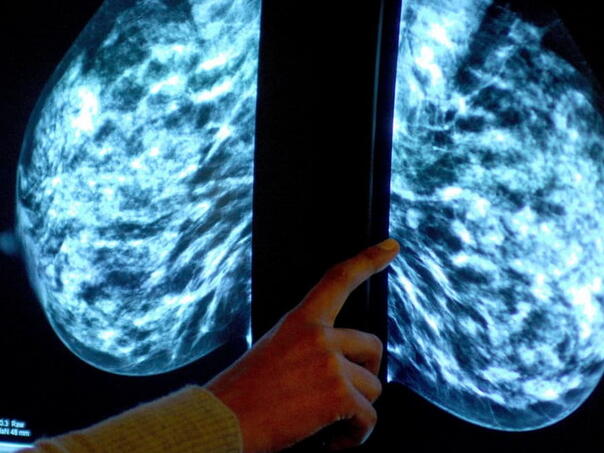

Capivasertib je prikladan za oboljele koje imaju određene genetske mutacije, prisutne kod otprilike polovice žena s hormonski ovisnim metastatskim rakom dojke – najčešćim oblikom ove bolesti, koji raste pod utjecajem estrogena.